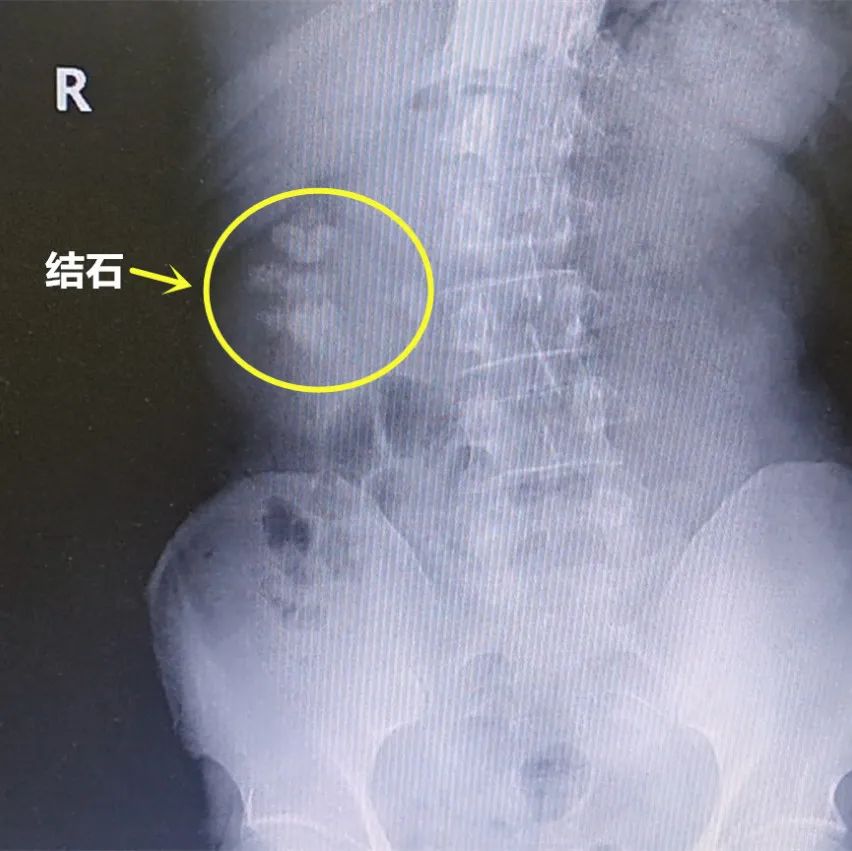

果然,经过X线检查发现王先生又出现了双侧肾结石和右侧输尿管结石,右肾内基本装满结石,考虑到患者结石大、数量多、且肾脏结构呈花瓣状,手术难度会很大,门诊医生不禁犯了愁,有心把患者转到条件更好的三甲医院又怕辜负了患者对我们的信任。庞栋主任带领全科医生慎重讨论后决定让患者入院进行手术治疗。

术前CT显示的结石

术前X片显示的结石